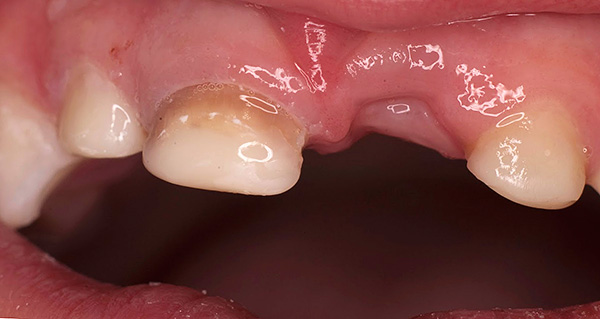

A fotografia abaixo mostra um exemplo da mordida cruzada anterior:

Mordida cruzada na região anterior - é diagnosticada quando um ou vários dentes estão em uma posição anormal, na maioria das vezes inclinados para o lado da língua, criando assim uma sobreposição nas costas. Por exemplo, um ou dois incisivos podem se cruzar.